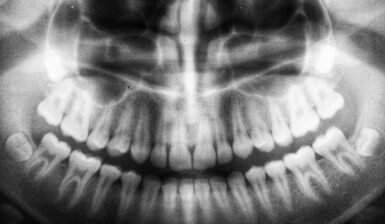

A full understanding of your dental health is essential to determine the best course of action for your wisdom teeth. Your consultant will use scans, physical exams, and their experience to assess the situation, identifying potential problems and judging whether removal is necessary.

Impacted wisdom teeth can lead to infection, pain, and swelling. Misaligned teeth make cleaning difficult, increasing the risk of decay, which can spread to neighbouring teeth. Further complications may include cysts, bone loss, nerve damage, or periodontitis.